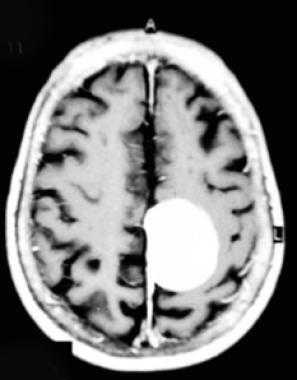

Метастазы в головном мозге.

Метастаз в головном мозге в динамике